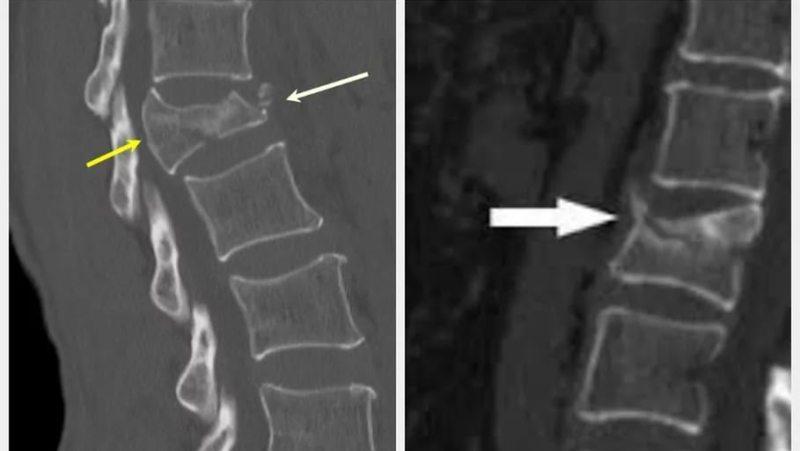

- рентгенографическое исследование пораженной зоны в двух или трех проекциях;

- компьютерная томография (КТ) и магнитно-резонансная томография (МРТ), которые позволяют более точно оценить характер травмы и необходимое лечение при оскольчатых или компрессионных переломах шейного отдела позвоночника.